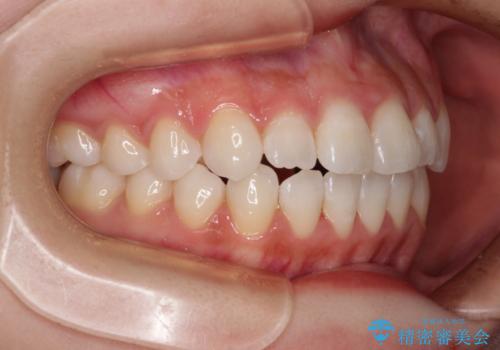

治療開始当初は舌の突出癖が改善されておらず、上下前歯の隙間がより顕著な状態となりました。

舌のトレーニングは、突出癖がなくなるまで必要であり、矯正治療後に突出癖が残ると、あっという間に隙間が空き、後戻りでデコボコとなってしまいます。